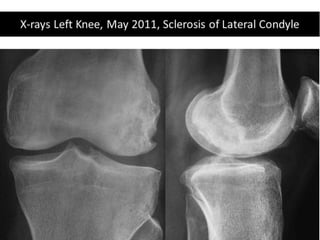

The document presents a detailed case study of a patient with transient osteoporosis of the hip (TOH) and spontaneous osteonecrosis of the knee (SONK) treated at Choithram Hospital & Research Centre in India. Over 20 years, the patient experienced multiple episodes of TOH and SONK with no history of trauma or co-morbidities, resulting in resolutions and recurrences of conditions. The information is intended for orthopedic surgery students and highlights personal experiences and case collections, with a disclaimer regarding content usage and potential controversies.